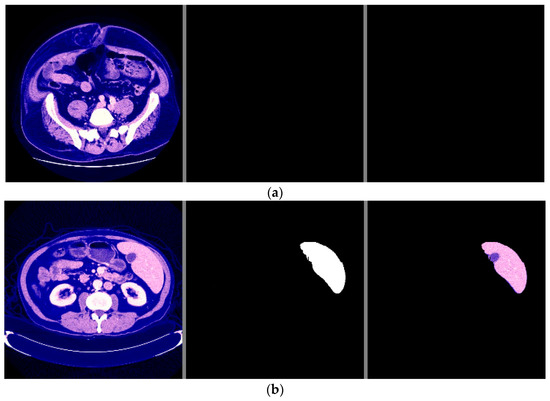

The visual examples of the results of the model for detecting liver cancer from the dataset are shown in Figure 16.

Figure 16.

The visual results of the second model for cancer detection on 3D-IRCADb-01 dataset: (a) normal case (no tumor detection); (b) abnormal case (tumor detection).

From the previous results mentioned in Section 3, it was observed that the first proposed method (the combination of DeeplapV3 and ResNet 50) achieved better accuracies than the second method (the combination of VGG-16, ResNet 50 V2, U-Net and LSTM) using both datasets. Therefore, we confirmed the first method to be our method. We also observed from the results that the first method obtained a high accuracy of 99.5% on small data (the case of the second dataset), which makes it more robust and efficient than other previous deep learning methods. In addition, when using the first dataset, as shown in Figure 7, it was observed that the first model could accurately detect cancer from the normal image. However, we can see from Figure 9 that the second model made some noise when detecting cancer from a normal image (as shown in Figure 9a). In terms of the second dataset (small data), we can observe from Figure 12 and Figure 16 that, when detecting cancer from the image, the two models detected cancer with some noise, but the first model was still better than the second model, with less noise. We employed the ReLU activation function in our models because it does not become active in all neurons at the same time. In addition, ReLU gives the highest accuracy, compared with other nonlinear activation functions, such as the Tanh activation function. Table 5 shows a performance comparison when using ReLU as an activation function and other nonlinear activation functions on the 3D-IRCADb-01 dataset.